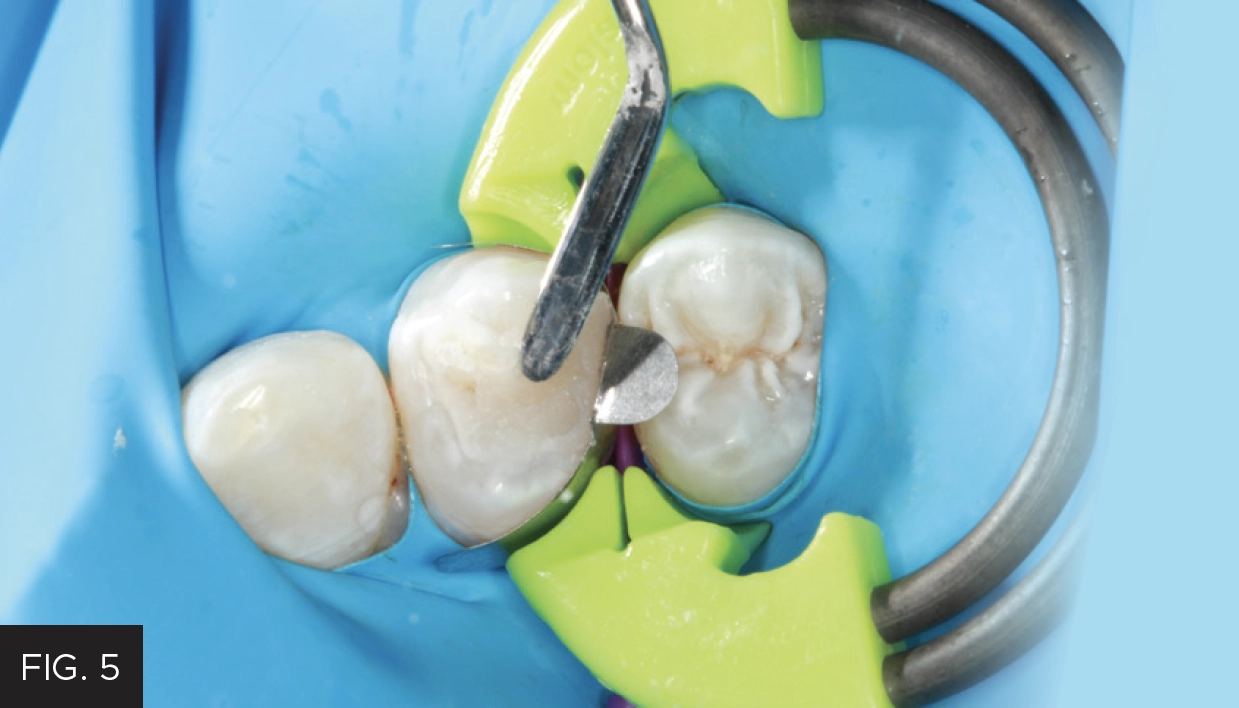

This clinical case highlights a common scenario. (FIG. 1) A Class II carious lesion was detected on the distal of #5. (FIG. 2) The patient was anesthetized via infiltration. Before preparation, a latex free rubber dam (True™ Dental Dam, Clinician’s Choice®) was placed to provide the first line of isolation.